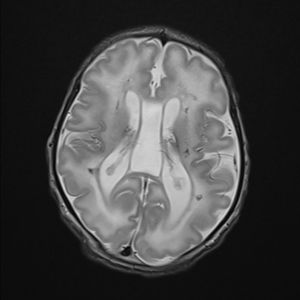

EL EXAMEN NEUROLÓGICO EN EL NEONATO

El examen neurológico (EN) es una herramienta clínica que nos permite aproximarnos a la evaluación funcional del sistema nervioso y tiene un enorme valor para establecer la naturaleza y localización de déficits funcionales del sistema nervioso central (SNC) y periférico (SNP).